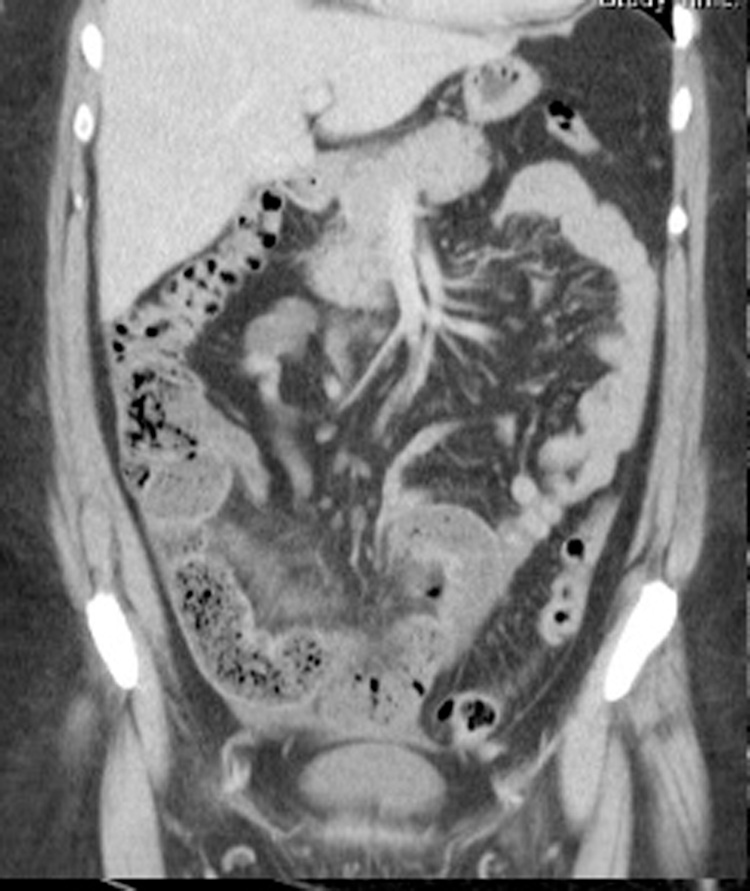

She had no previous history of lower abdominal pain or bowel obstruction. Her vital sign observations, urinalysis and full blood count were unremarkable. Her physical examination demonstrated a soft but distended abdomen with lower abdominal tenderness, maximally over the right-lower quadrant. CT abdomen demonstrated a distal small bowel obstruction with faecalisation and transition point close to the terminal ileum, without any discrete mass, Fig. 1.

Fig. 1.

Coronal CT image demonstrating acute small bowel obstruction with a transition point and faecalisation within the distal ileum.